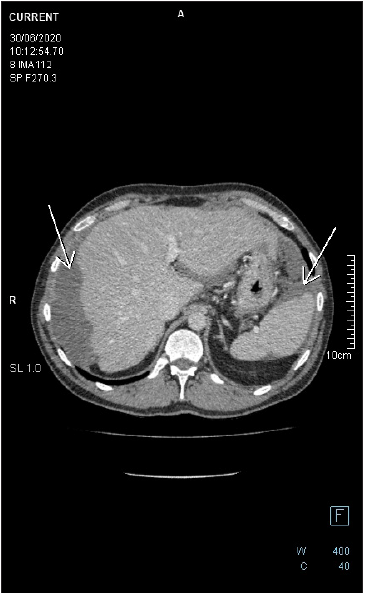

Figure 6: Follow up axial-CECT of the upper abdomen reveals perihepatic and perisplenic mucinous deposits. There is a faint soft tissue component in the perihepatic lesion, the wall of which is enhancing with no appreciable septation nor calcification. There is no fat stranding in the adjacent fat tissue. Lesions are noticed to be stable on CECTs performed in years 2019 and 2020.

Microscopic study of the slides revealed low grade appendiceal mucinous neoplasm, LAMN. Pathomorphological stage was diagnosed as pT4a Nx since it has perforated visceral peritoneum. The lesion was located within the wall of the caecum and the proximal part of the appendix (Figure 6). There were some acellular mucin pools in mesentery and in the intestinal wall. Appendiceal wall shown widespread epithelial denudation with the atrophy of underlying lymphoid tissue. Multiple blocks were required to demonstrate tumor cells. Focally appendiceal mucosa presented epithelium with villous morphology covered with cells mostly without atypia. There were some neoplastic epithelial cells with low grade dysplasia lying on fibrous stroma. The greatest part of the lesion consisted of the epithelial cells lying in the lakes of mucus within the lumen of the appendix. High grade dysplasia was not found.